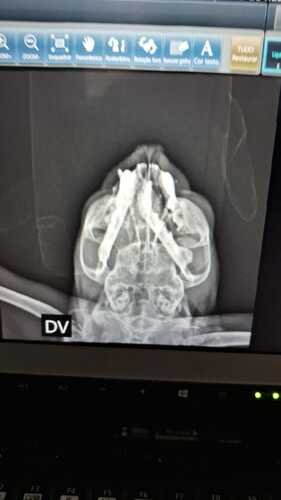

Recentemente eu sofri um incidente que quebrou a minha mandíbula e, com isso eu necessito fazer uma cirurgia com urgência.

Por conta da lesão, eu não consigo me alimentar e minha respiração está sendo dificultada.